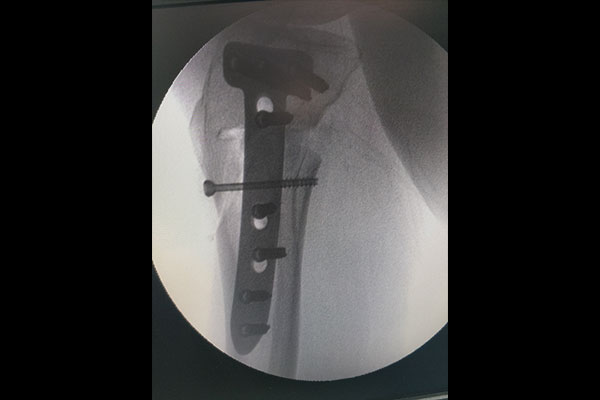

STEPS OF HTO